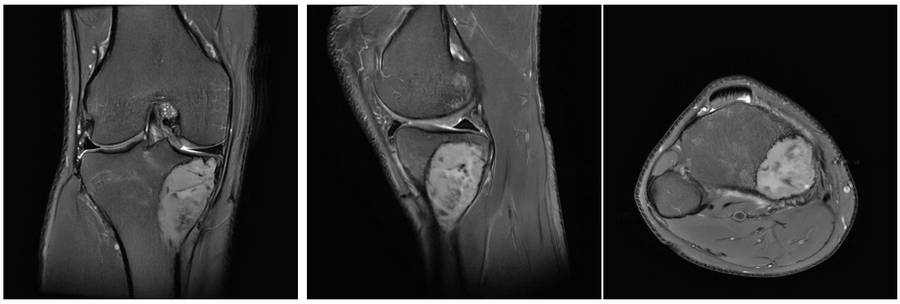

Ameliyat Öncesi: MR’da lezyonun sınırlarının düzenli ve heterojen kitle olduğu görülmekte